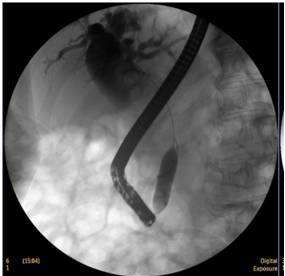

胆道疾病诊疗:主要以现代内镜外科为特色,通过微创手术的方法解决胆道疾病,利用十二指肠镜(治疗性ERCP)、胆道镜来完成的,大部分常见胆道疾病都是治疗性ERCP的适应证,如胆道结石、梗阻性黄疸、胆道蛔虫、胆道肿瘤、胆源性胰腺炎等。能极大避免胆道结石的残留与复发;同时,我科积累了上千例的腹腔镜胆囊切除(LC)的经验,还开展了腹腔镜肝叶切除、肝囊肿开窗引流、胆总管切开取石、胆道探查、胆总管切开I期缝合等手术,形成了自己的特色。对于晚期胆道肿瘤,通过胆道支架置入,提高了患者的生存质量;能早期解除胆源性胰腺炎的病因,降低了急性重症胰腺炎的死亡率。对复杂型肝胆管结石症、多发性肝内胆管结石采用手术中纤维胆道镜、超声定位、冲击波碎石等方法并用,对肝胆管结石进行彻底清除,大大减少了残石率及再发率。